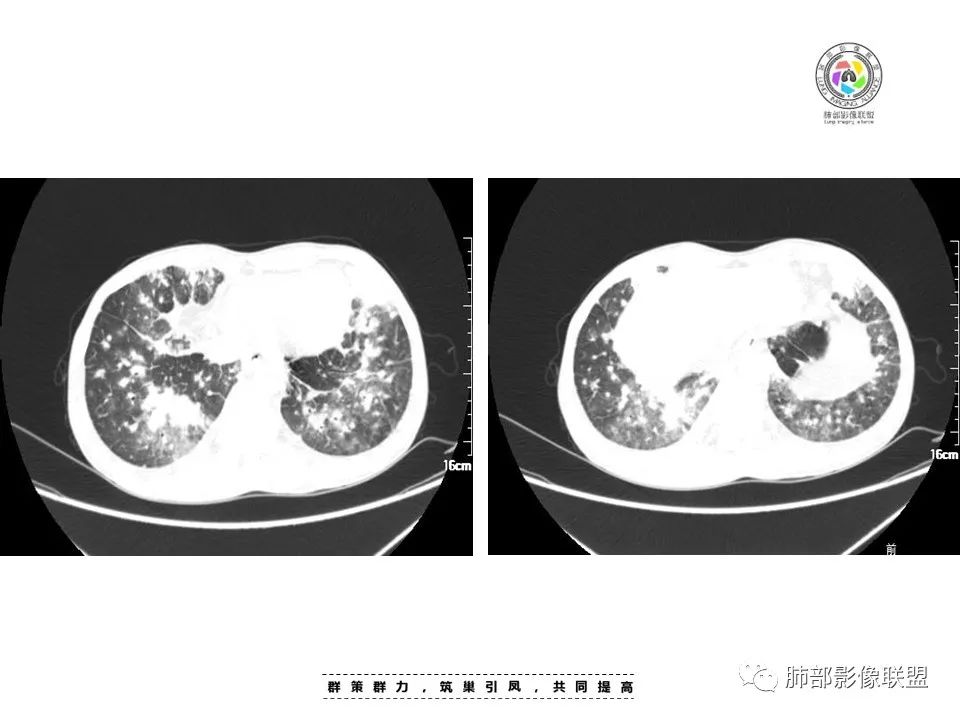

周一晚读病例:男性45岁,发热、纳差,全身散在暗紫色皮疹,结合CD4,符合HIV;肺部影像表现:两肺散在实性结节及磨玻璃密度影,实性结节伴晕征,部分沿支气管血管束分布,支气管血管束增粗,以两肺下叶为著,类似火焰征,双侧胸腔少量积液;首先考虑卡波西肉瘤,鉴别淋巴瘤增值性病变,淋巴瘤样肉芽肿/淋巴瘤,最后挂上马尔尼菲青霉菌病。

两肺弥漫性性结节状、小片状及片状带晕的病灶,煎蛋征、点晕征,主要分布两肺中下叶,病灶周围小叶间隔增厚呈网格状影,部分病灶累及胸膜,伴两侧胸膜增厚。

2.本例双肺小叶间隔增厚明显,多发结节影及片状实性密度影,沿血管支气管束分布为主,两侧较为对称,病灶多环以磨玻璃晕,边界不清。

双侧胸腔少量积液。双肺门及纵隔未见明确肿大淋巴结,纵隔结构间隙模糊。

3.有学者将这种具有沿双肺支气管束分布的实性密度片影描述为“火焰征”,认为具有一定特征性,单就影像表现而言,这种影像表现也可以见于其他病损或多种病理改变的叠加。

1.结节型:两肺沿支气管血管束分布的结节影,呈火焰状或星芒状、挂果征,局部周围出血磨玻璃影(肺泡出血或水肿)。

2.支气管血管束增粗型:

肺门周围支气管壁呈“套袖样”改变。

3.肺炎渗出型:

斑片渗出影,部分融合呈“火焰样”,同时有火焰样结节,小叶间隔增厚等表现。

还可以有纵隔及腋下淋巴结增大,胸腔积液等表现。